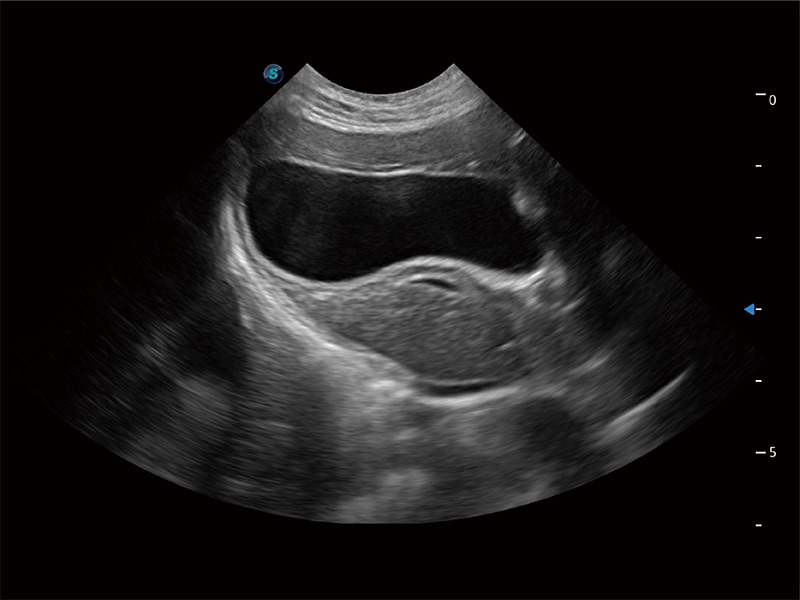

高性能和先进的临床应用工具可以为动物医生提供临床信心。ProPet 80 搭载了先进的腹部和浅表应用工具,帮助医生在日常临床实践中发挥前所未有的作用。

极大提升超低速微细血流的检出能力,同时更精准地滤除软组织和超声信号,为兽用医生提供以往无法通过常规血流获得的疾病诊断信息。

在传统二维血流成像的基础上,呈现血流的立体感,具有动感的生命力之美。即便是微小的血管也能轻松应对,提高了血流的视觉敏感性。